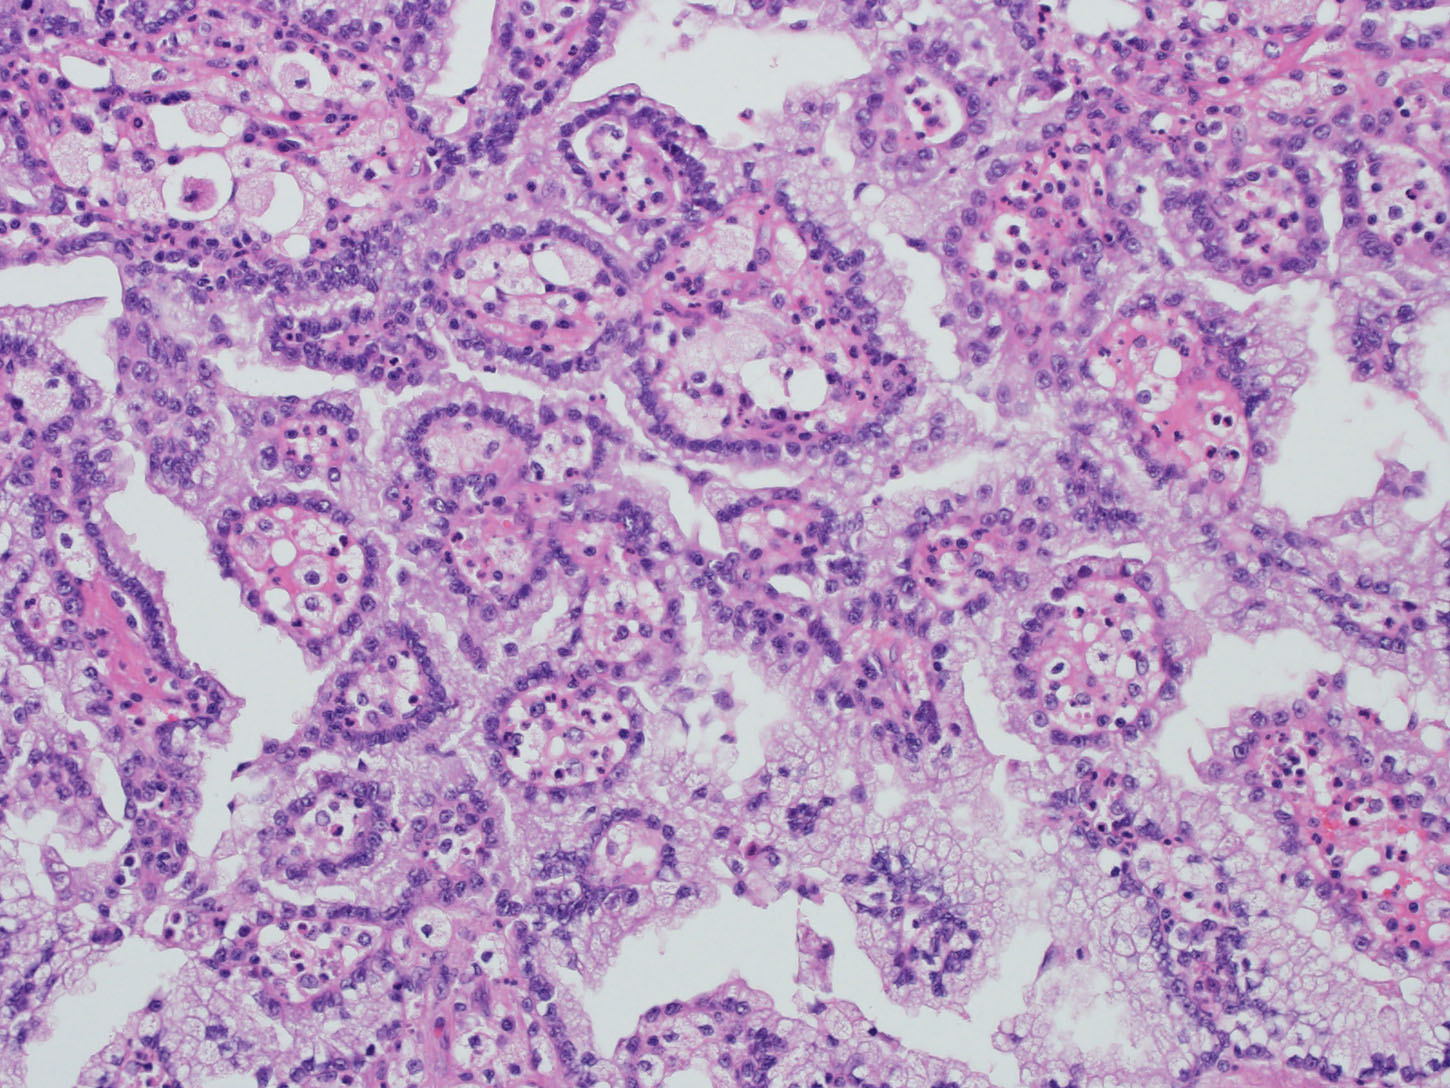

Consensus grade: Papillary RCC (Type 1)

| Pathologist 1 | Papillary RCC (Type 1) | Not typical |

cytoplasmic clearing |

| Pathologist 2 | Papillary RCC (Type 2) | Not typical | |

| Pathologist 3 | Papillary RCC (Type 1) | Typical | |

| Pathologist 4 | Renal cell carcinoma, unclassified | Not typical | |

| Pathologist 5 | Insufficient tumor for diagnosis | Not typical | |

| Pathologist 6 | Renal cell carcinoma, unclassified | Not typical |

need more images |

| Pathologist 7 | Papillary RCC (Type 2) | Not typical | |

| Pathologist 8 | Papillary RCC (Type 1) | Typical | |

| Pathologist 9 | Papillary RCC (Type 1) | Typical | |

| Pathologist 10 | Papillary RCC (Type 1) | Not typical | |

| Pathologist 11 | Papillary RCC (Type 1) | Typical | |

| Pathologist 12 | Papillary RCC (Type 1) | Not typical | |

| Pathologist 13 | Papillary RCC (Type 1) | Typical | |

| Pathologist 14 | Papillary RCC (Type 1) | Not typical |

papillary RCC type 1 with clear cell changes |

| Pathologist 15 | Renal cell carcinoma, unclassified | Not typical |

type 1 PRCC with clear cells! |

| Pathologist 16 | Papillary RCC (Type 1) | Not typical | |

| Pathologist 17 | Papillary RCC (Type 2) | Not typical | |

| Pathologist 18 | Papillary RCC (Type 1) | Typical | |

| Pathologist 19 | Papillary RCC (Type 1) | Not typical |

This is for me PRCC NOS with "hibernoma-like" cells |

| Pathologist 20 | Papillary RCC (Type 1) | Not typical | |

| Pathologist 21 | Papillary RCC (Type 1) | Not typical | |

| Pathologist 22 | Papillary RCC (Type 1) | Not typical | |

| Pathologist 23 | Papillary RCC (Type 1) | Not typical |